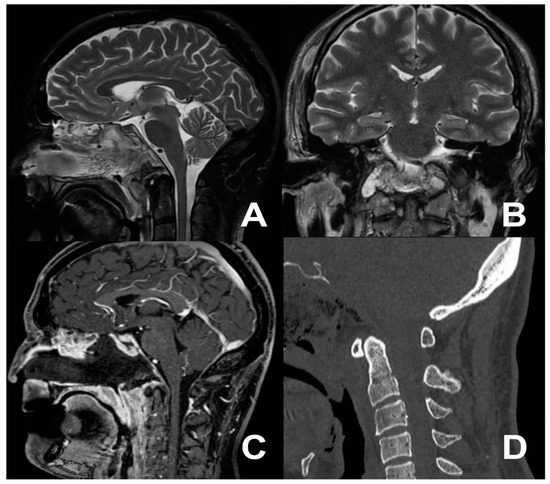

3.3. Second Case: One-Stage Combined Submandibular Retropharyngeal Approach and Posterior Midline C1-C2 Fusion